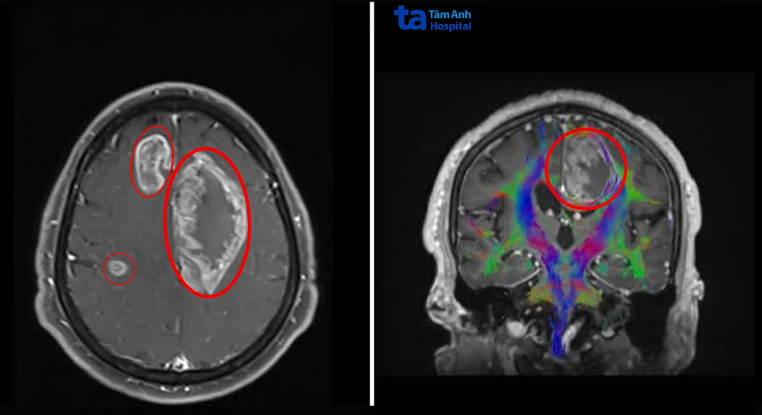

Ông Giang có biểu hiện nói bất thường từ hai tháng trước, gần đây tay chân yếu nên cầm đồ vật bị rơi và đi lại loạng choạng, đến Bệnh viện Đa khoa Tâm Anh TP HCM khám. Kết quả chụp MRI 3 Tesla ghi nhận ông Giang có đến ba khối u nằm trong não. Khối lớn nhất ở thùy trán trái, kích thước lớn như quả cam, 7 cm. Hai khối u nhỏ hơn 3,5 cm và 1,3 cm ở thùy trán và thùy đỉnh phải.

"Trường hợp u não đa ổ như ông Giang phức tạp do các khối u nằm sâu, lan rộng qua cả hai bán cầu đại não", ThS.BS.CKII Chu Tấn Sĩ, Trưởng khoa Phẫu thuật Thần kinh, Trung tâm Khoa học Thần kinh, nói, thêm rằng các ổ u xâm lấn vào thân thể chai (trung tâm truyền tín hiệu liên bán cầu), chèn ép não thất bên trái và đè lên các đường dẫn truyền thần kinh quan trọng như bó tháp (kiểm soát vận động). U nằm gần những vùng chức năng nhạy cảm liên quan đến ngôn ngữ, vận động và hành vi, nếu không được xử lý sớm, u phát triển có thể làm tăng áp lực nội sọ, tụt não, hôn mê, tử vong.

Ảnh chụp MRI 3 Tesla ghi nhận ba khối u lớn (khoanh tròn) trong não ông Giang. Ảnh: Bệnh viện Đa khoa Tâm Anh